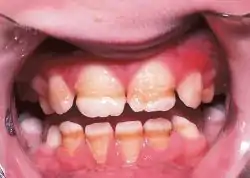

Enamel hypoplasia is a defect of the teeth in which the enamel is deficient in quantity,[1] caused by defective enamel matrix formation during enamel development, as a result of inherited and acquired systemic condition(s). It can be identified as missing tooth structure and may manifest as pits or grooves in the crown of the affected teeth, and in extreme cases, some portions of the crown of the tooth may have no enamel, exposing the dentin.[2] It may be generalized across the dentition or localized to a few teeth. Defects are categorized by shape or location. Common categories are pit-form, plane-form, linear-form, and localised enamel hypoplasia.[3][4][5] Hypoplastic lesions are found in areas of the teeth where the enamel was being actively formed during a systemic or local disturbance. Since the formation of enamel extends over a long period of time, defects may be confined to one well-defined area of the affected teeth. Knowledge of chronological development of deciduous and permanent teeth makes it possible to determine the approximate time at which the developmental disturbance occurred.[6] Enamel hypoplasia varies substantially among populations and can be used to infer health and behavioural impacts from the past. Defects have also been found in a variety of non-human animals.[7][8][9]

Irreversible enamel defects caused by an untreated celiac disease. They may be the only clue to its diagnosis, even in absence of gastrointestinal symptoms, but are often confused with fluorosis, tetracycline discoloration, or other causes.[10][11][12] The National Institutes of Health include a dental exam in the diagnostic protocol of celiac disease.[10]

Enamel hypoplasia is a risk factor for dental caries in children including early childhood caries (ECC), which continues to be a burden for many children. This association has been identified as significant and independent, and is believed that the formation of pits and missing enamel provides a suitable local environment for adhesion and colonization of cariogenic bacteria. Historically, enamel hypoplasia has been under-appreciated as a risk factor for ECC.

Developmental defects in enamel that affect tooth appearance in the esthetic zone (i.e. upper front teeth) may cause individuals to experience social embarrassment or anxiety regarding the appearance of their teeth.